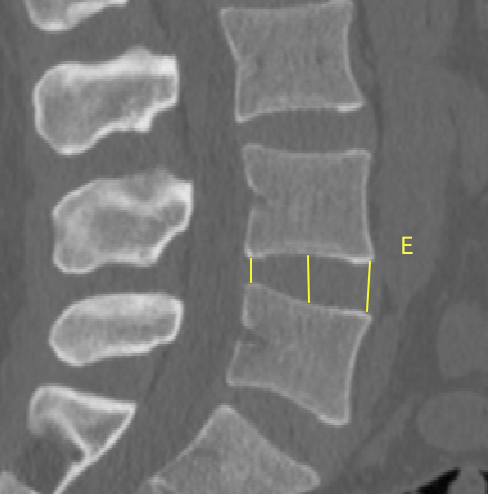

2、通過術前CT測量L4-5節段手術部位的(1)上位椎體后下角水平方向到關節突關節的距離(A);(2)纖維環后緣的中點水平方向到關節突關節的距離(B);(3)下位椎體后上角水平到關節突的距離(C);(4)上位椎體的椎弓下切跡與下位椎體椎弓上切跡連線的距離(D),圖 6;(5)在手術節段的棘突矢狀位CT層測量椎間隙高度(E),圖 7;(6)在手術節段的關節突關節橫截面CT層測量關節突間距離(F),圖 8,再通過術中及術后CT判斷患者椎間孔成型級別,將A-F測量數據與5級成型中的各級別成型進行相關性分析。

圖 7 E的測量方式 |